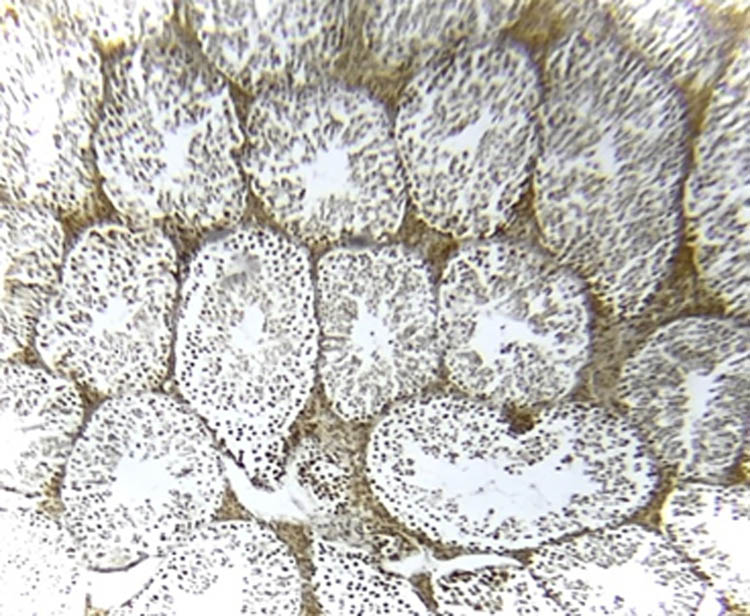

3.8 NOS immunohistochemistry in testicular tissue

Figures 7–11 represent the immunoreactivity of NOS in all groups. The immunoreactivity of NOS was significantly greater in mice treated with CGS (Figure 8), CGM (Figure 9), and CGA extracts (Figure 10) than in the control (Figure 7) and untreated diabetic (Figure 11) groups. In the untreated diabetic group, normal testicular architecture (seminiferous tubules) was destroyed and replaced by adipose tissue. Furthermore, the immunoreactivity of the enzyme in the untreated diabetic group was the lowest (Figure 11). Treatment with different C. gileadensis extracts restored the normal architecture of testicular tissue in diabetic mice.

NOS immunoreactivity in the control group.

NOS immunoreactivity in the diabetic C. gileadensis sap-treated group.

NOS immunoreactivity in the diabetic C. gileadensis methanol-treated group.

NOS immunoreactivity in the diabetic C. gileadensis acetone-treated group.

NOS immunoreactivity in the untreated diabetic group.